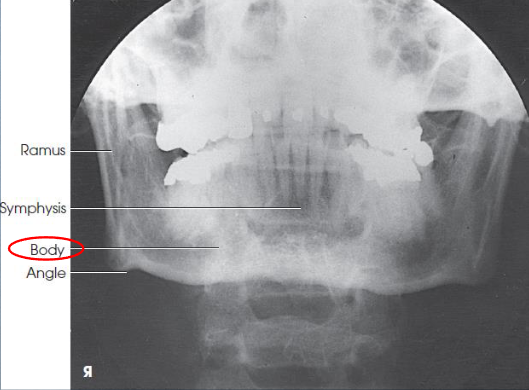

PA mandibular rami image criteria

mandibular body and rami

central part of body not well shown due to superimposition

shows medial or lateral displacement of fragments in fractures of the rami

no rotation or tilt:

symmetric mandibular body and rami

MSP of head aligned with long axis of collimated field